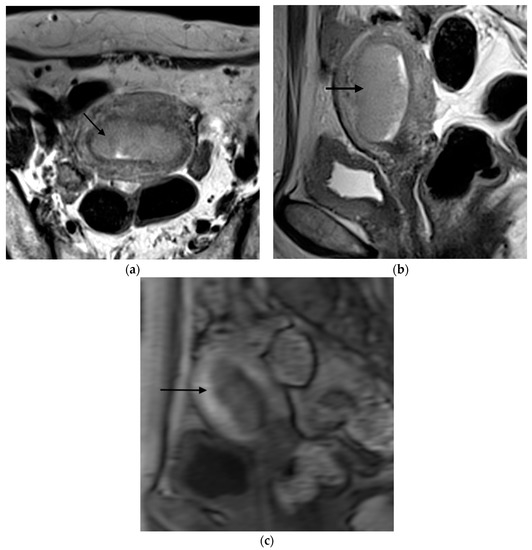

Figure 1, Figure 2, Figure 3 and Figure 4 depict the representative MRI images of tumors with < 50% myometrial invasion and ≥50% myometrial invasion, as well as the representative combined T2WI+DCE-MRI images for false-positive and false-negative cases, respectively. The diagnostic performance of MRI in predicting the depth of myometrial invasion is presented in Table 2 and Table 3. The depth of myometrial invasion (any depth) was correctly determined in 75% (n = 24) and 78% (n = 25) of cases on T2WI and DCE-MRI alone, respectively, whereas the percentage increased to 91% (n = 29) of cases when the T2W images were read together with those obtained by DCE-MRI.

Figure 1. Representative MRI images of endometrial carcinoma with <50% myometrial invasion. (a) Axial T2WI, (b) sagittal T2WI, and (c) sagittal DCE-MRI images during the early acquisition stage. Tumors (arrow) with <50% myometrial invasion presented as iso- to mildly hyperintense on T2WI compared to the myometrium (a,b) with an intact junctional zone. On DCE-MRI, the tumors appeared as hypointense masses compared to the adjacent myometrium with intact subendometrial enhancement (SEE), indicating a tumor that is confined to the endometrium (c). Abbreviations: MRI, magnetic resonance imaging; dynamic contrast-enhanced magnetic resonance imaging (DCE-MRI); T2WI, T2-weighted imaging.